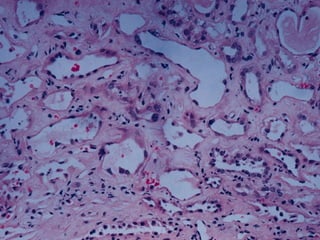

Casts in distal & collecting tubules

 The tubular vacuolization and dilation .

 This is representative of acute tubular necrosis (ATN(

ATN morphology  Anadditional feature is the presence of casts in distal & collecting tubules.  They are composed of Tamm-Horsfall protein (secreted normally( by renal tubules.  When crush injuries results in ATN the casts are composed of myoglobin  If the patient survive epithelial regeneration become apparent

Casts in distal& collecting tubules

 The tubularvacuolization and dilation .  This is representative of acute tubular necrosis (ATN(